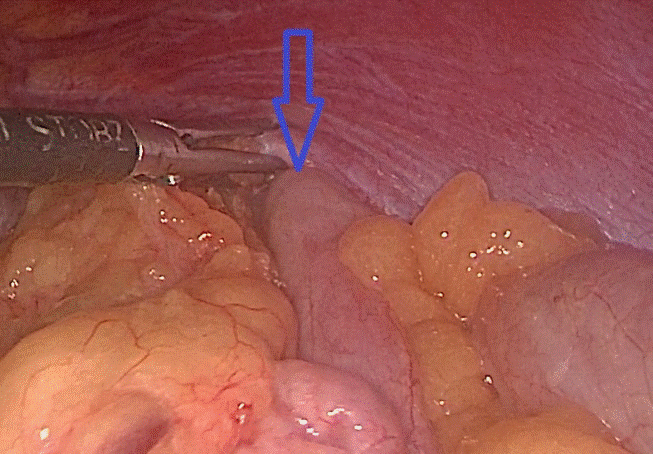

Tại đây, bệnh nhân H. đã được chỉ định mổ nội soi để sửa tổn thương và phục hồi cơ hoành. Khi đưa máy soi vào ổ bụng, phẫu thuật viên nhận thấy gần toàn bộ đại tràng ngang, lách, dạ dày và mạc nối lớn đã chui qua cơ hoành lên khoang màng phổi bên trái. Sau khi đưa các tạng trên trở lại ổ bụng, tổn thương cơ hoành bên trái lộ rõ là một lỗ khuyết rộng khoảng 6×8 cm. Đây chính là nguyên nhân gây ra thoát vị, kết hợp với tiền sử có chấn thương, chẩn đoán trong mổ là thoát vị hoành trái do vỡ cơ hoành. Cơ hoành vỡ đã được các phẫu thuật viên khâu phục hồi kín, ca mổ diễn ra trong 1 giờ 30 phút. Sau mổ, bệnh nhân ổn định, hết đau ngực, khó thở, chụp phim X.quang kiểm tra thấy phổi nở tốt, không còn hình ảnh thoát vị. Bệnh nhân H. được ra viện sau 6 ngày với sẹo mổ rất nhỏ của phẫu thuật nội soi.

Ảnh 3: Đại tràng chui qua lỗ thoát vị lên trên ngực trái